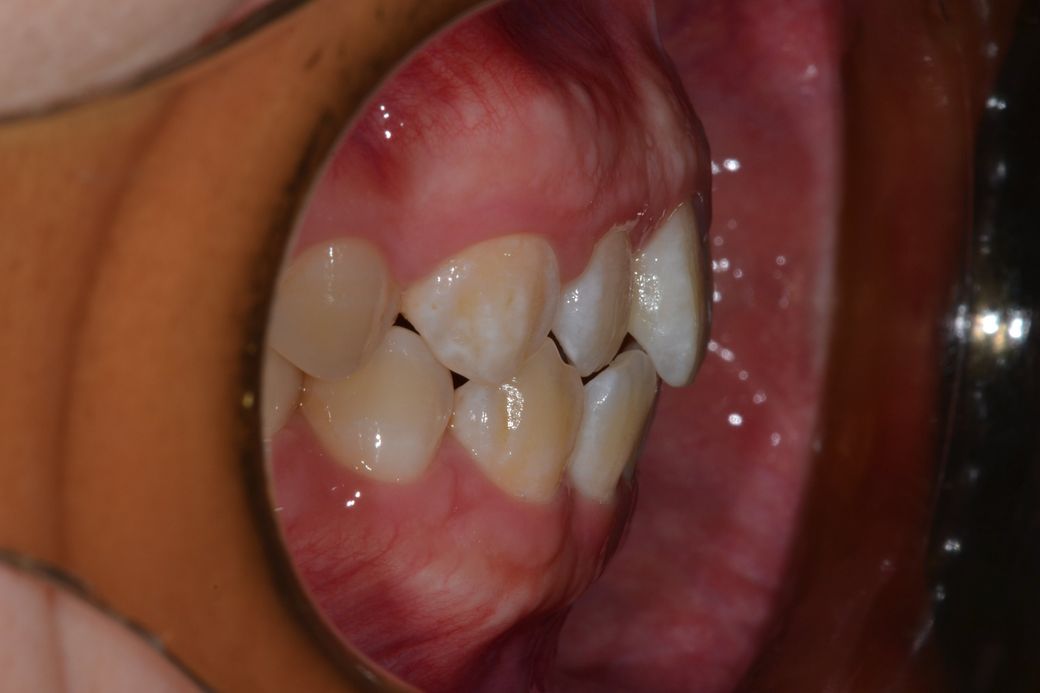

왼쪽2

오른쪽1

왼쪽이 제1소구치쪽부터 교합이 아주 이상적인 교합은 아닙니다. 또한, 오른쪽 2번째 치아는 원래 위 치아가 아래치아를 덮어야하는데, 그렇지 않고 치아끼리 바로 닿습니다. 이 경우 치아에 무리가 갈 수 있습니다.

하지만 사진과 같이 오른쪽 2번째 윗니와 아랫니가 절단교합이 되어 있으면 치아가 다 내려오지 않아서 공간이 보일수 있어요.

왼쪽 소구치와 대구치는 사진으로만 보기에는 정상적으로 교합하고 있는것으로 보입니다.